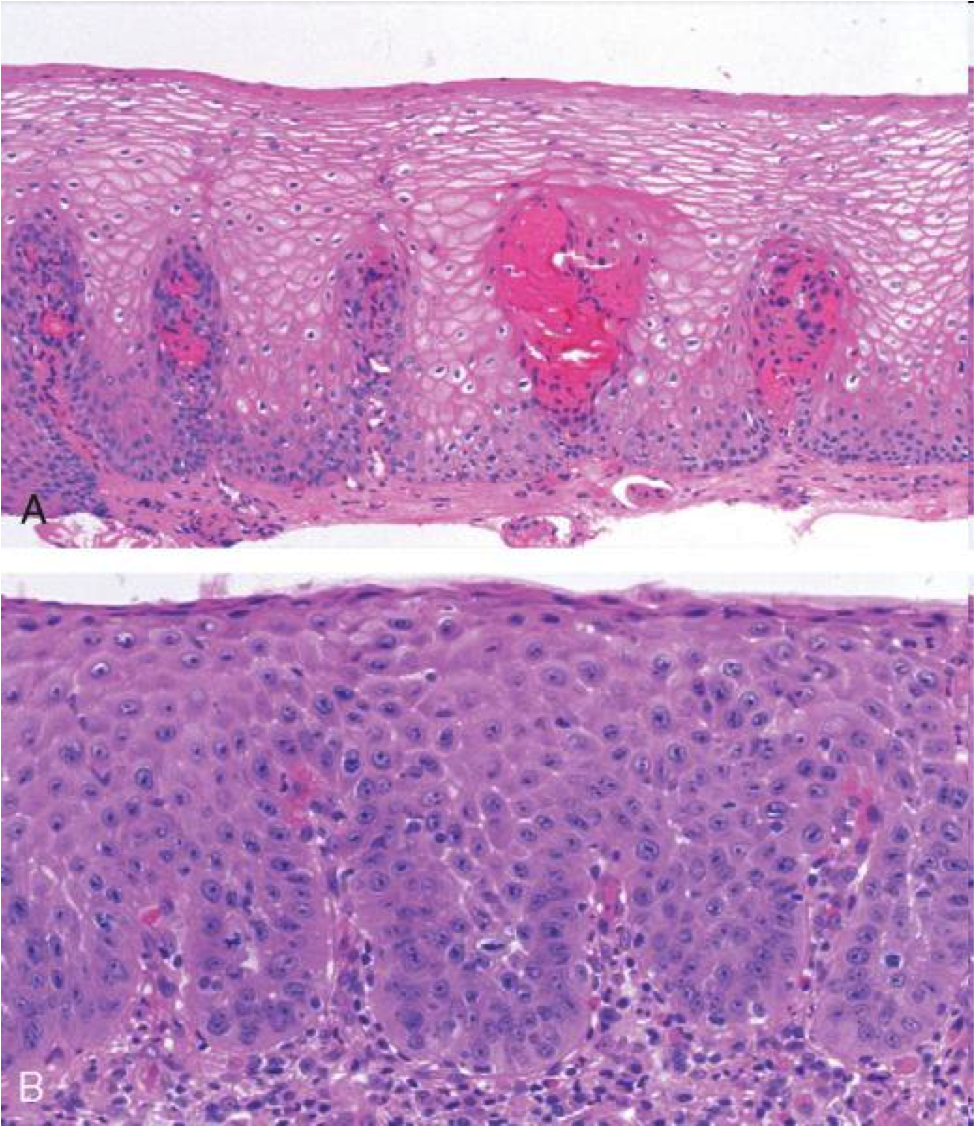

Histo of normal esophagus

- stratified nonkeratinizing squamous epithelium

- Z-line (squamocolumnar junction): mucosal junction of squamous and columnar epithelium, may not correspond to GE junction when columnar metaplasia has occured

normal gastroesophageal junction

stratified sqaumous of esophagus

simple columnar of gastric cardia

GERD on bottom

squamous proliferation, papillae elongation, basal cell hyperplasia, inc. inflammation in lamina propria, decreased surface maturation

Note: biopsy findings are not specific! cannot make diagnosis w/ biopsy alone must have clinical info as well